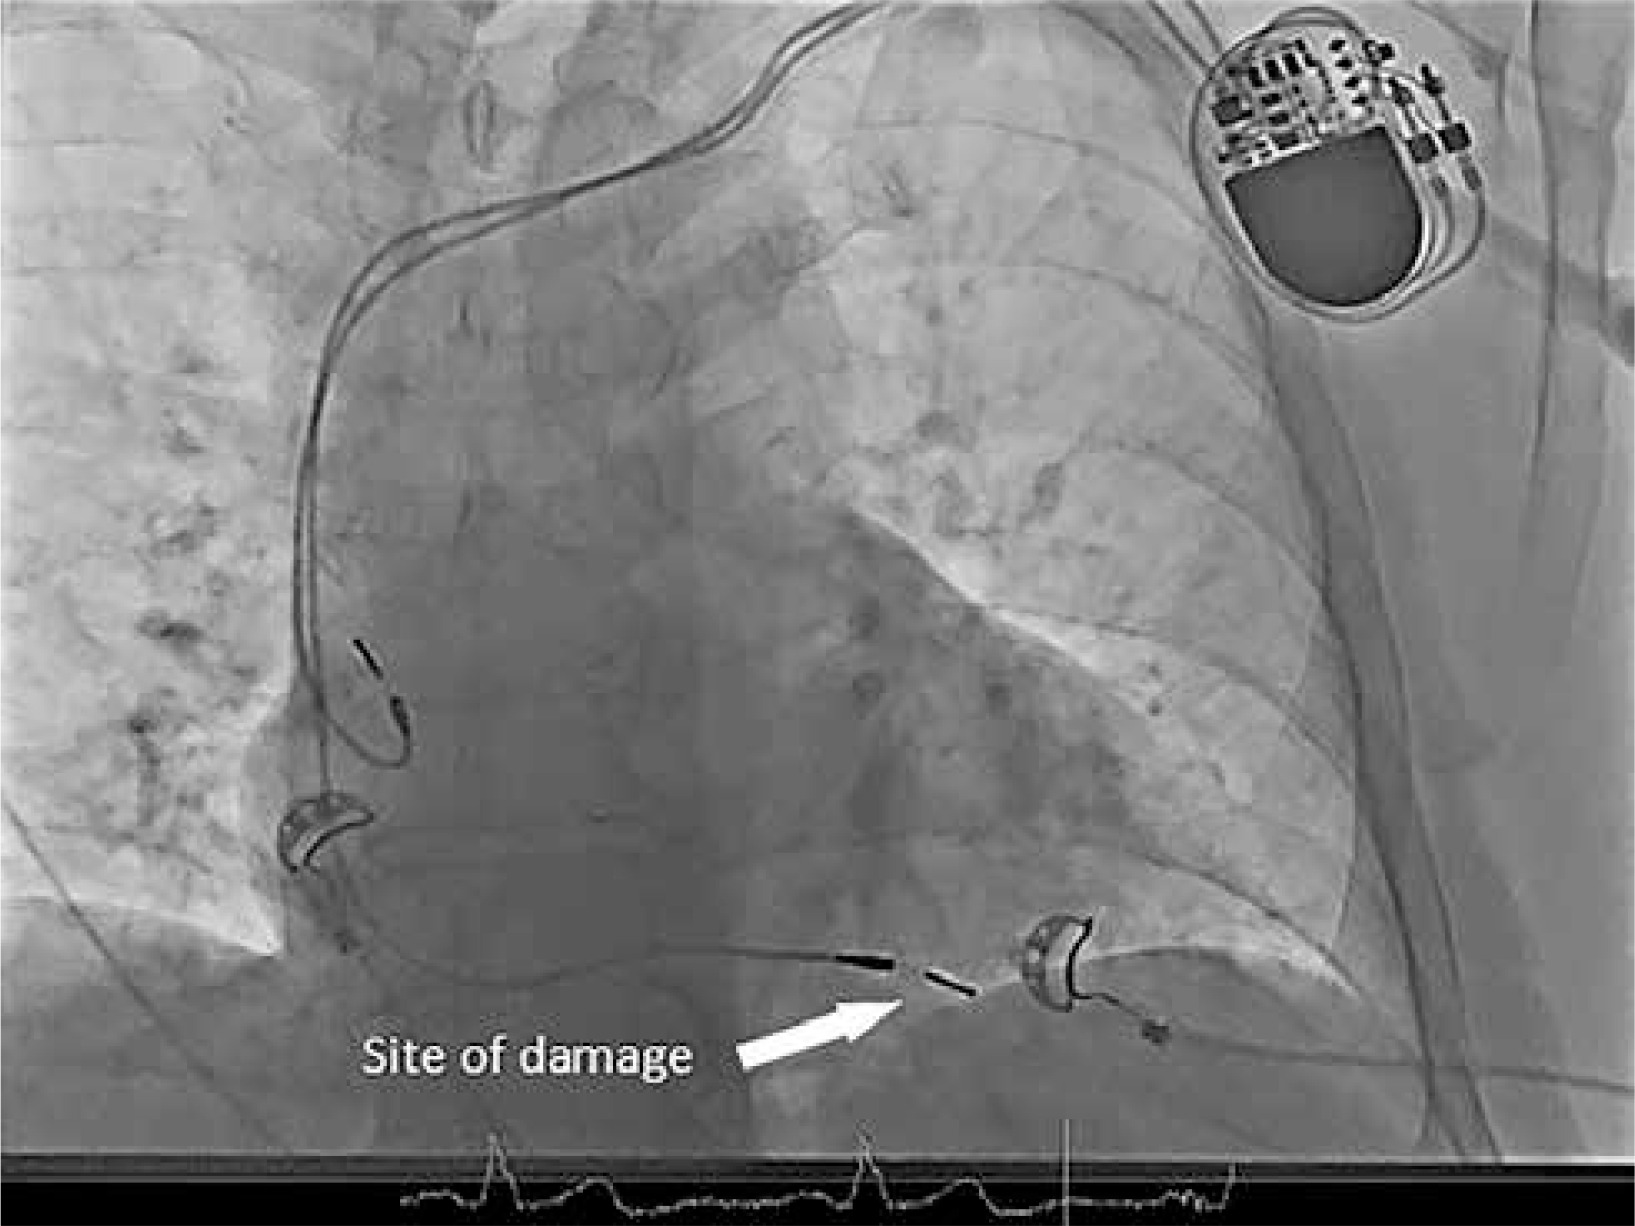

The patient’s medical background was complex, with comorbidities including hypertension, type 2 diabetes, obesity (body mass index (BMI) 37.97 kg/m2), and bilateral hip osteoarthritis. Although the patient attended regular follow-ups, he did not fully adhere to activity restrictions for his left shoulder, potentially impacting device function. Given the ongoing issues with lead impedance and stimulation thresholds, options were discussed, and the patient ultimately chose TLE over adding a new lead. The TLE was conducted in a hybrid operating room to enable rapid transition to surgery if necessary. The RV lead was removed using an 11 Fr Evolution mechanical rotational sheath, which offers high control during extractions (Figure 1).

Figure 1

Placement of the electrode in the right ventricle, illustrating the site of perforation during transvenous lead extraction (TLE)